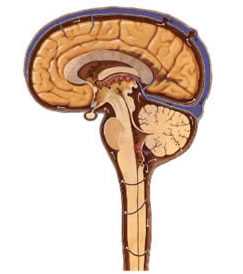

Слайд Цереброспинальная жидкость

Вырабатывается сосудистыми сплетениями желудочков мозга.

Регуляция осуществляется через нервную систему рефлекторным путем - раздражение через изменение давления в желудочках или изменение химического состава жидкости.

Ликвор в чистом виде - в желудочках мозга.

Ликвор субарахноидальных пространств: желудочковая жидкость +продукты обмена веществ, выделяемые паренхимой мозга и периферическими нервами.

Желудочковая и субарахноидальная жидкости отличаются по составу!

Мягкие мозговые оболочки в выработке ликвора не участвуют, но влияют на состав путем выделения или всасывания различных веществ.

В сутки секретируется около 500 мл ликвора(изменяется в течение суток).

Обновление ликвора - 5-6 раз в сутки.

Выработка спинномозговой жидкости (ликвора) осуществляется грануляциями в желудочках головного мозга.